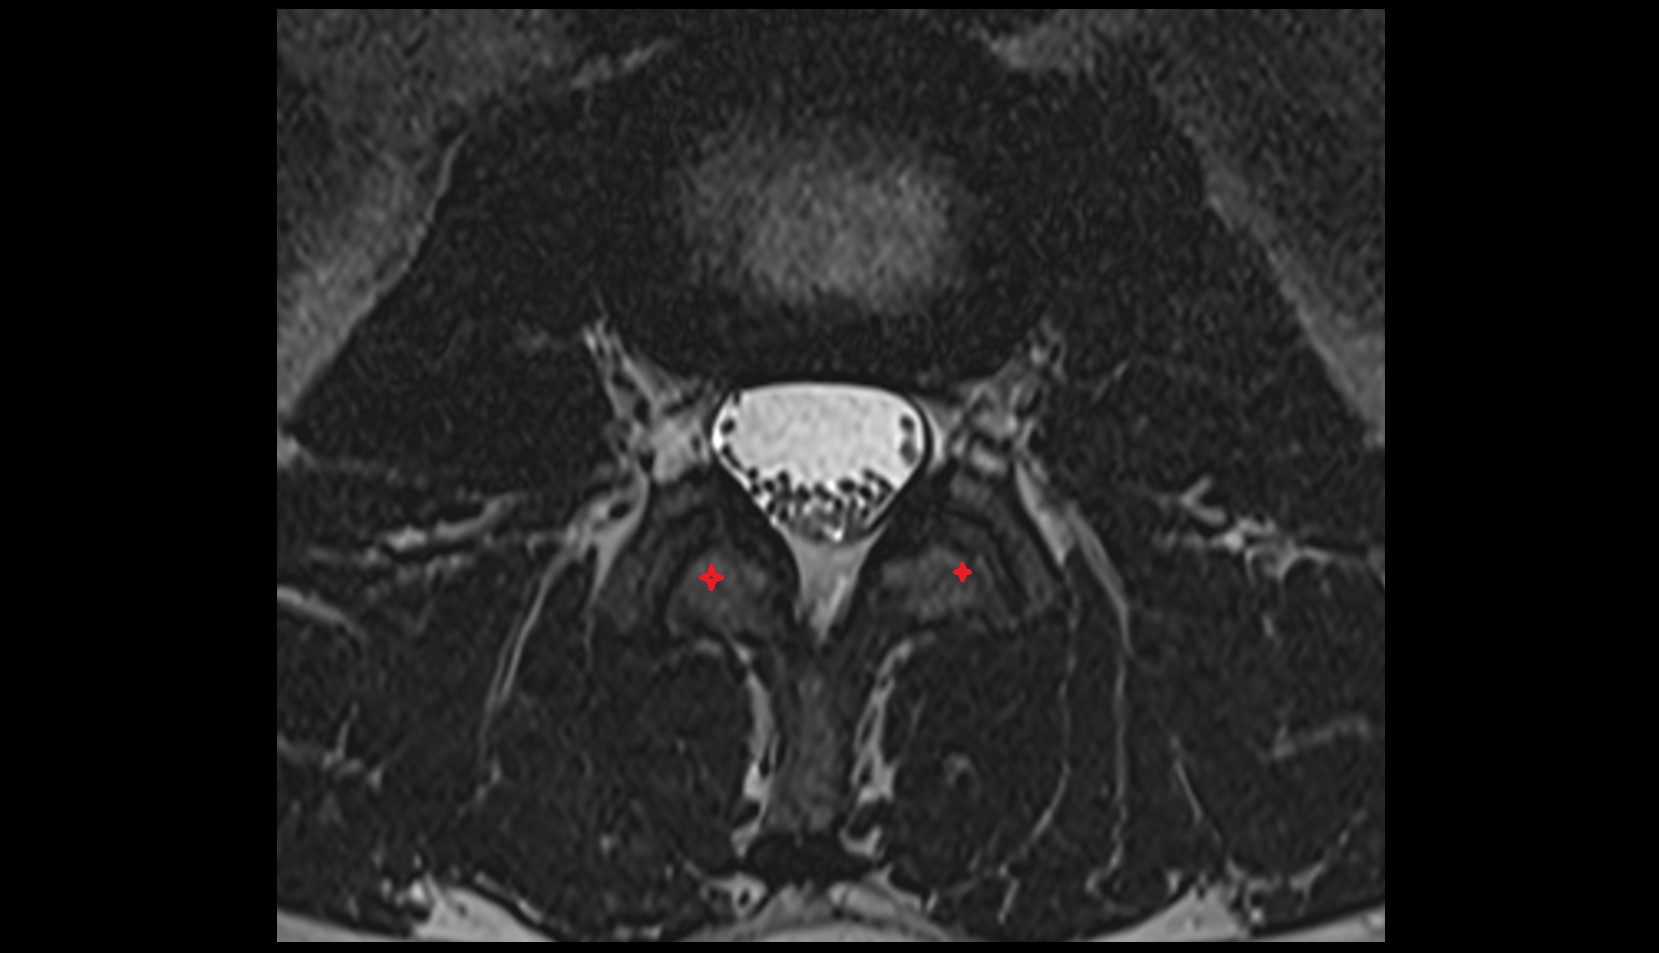

- Traversing nerve root of spinal nerve

- Exiting nerve root of spinal nerve

- Dorsal traversing nerve root

- Ventral traversing nerve root

- Dorsal exiting nerve root

- Ventral exiting nerve root